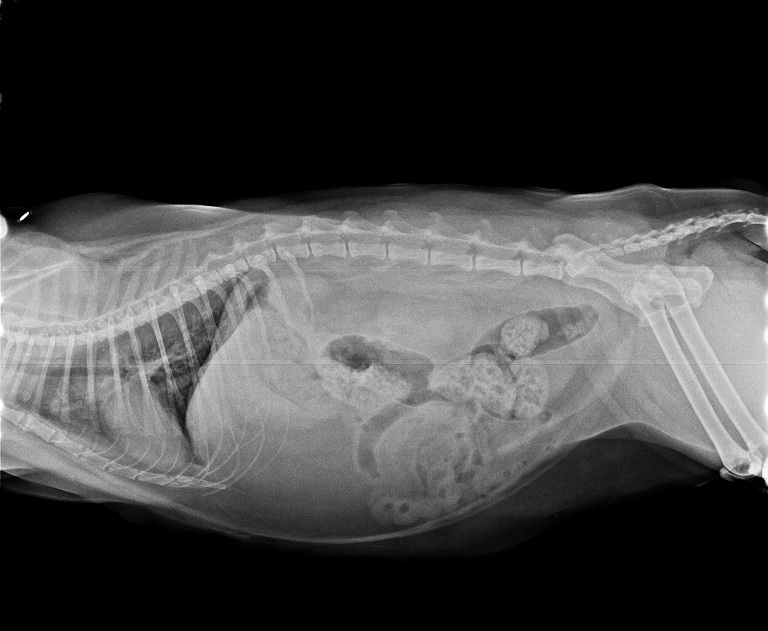

在拍X光照檢視後確認並沒有誤吃奇怪的東西,

肺部雖然有點混濁的情況但不是太嚴重,

並且再拍第二次X光照時發現已經到了肺炎的程度,